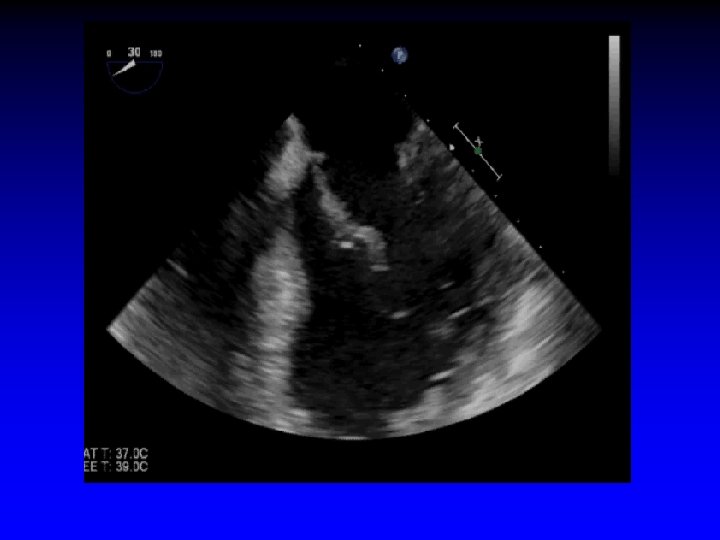

6. Leaflet Grasping Echo Guidance • Advance clip into LV just below the leaflet edges prior to grasping • Grip arms placed in grasping position (approximately 120º) • Pull back during systole to capture leaflets Midesophageal long-axis view

5. Advancing Mitra. Clip into LV • Imaged best with X-plane imaging (intercommissural view and LVOT view) • Reassess orientation of clip (Clip may rotate during “dive” into LV) • Look for: - Perpendicular alignment to coaptation line - Both leaflets moving freely above clip arms